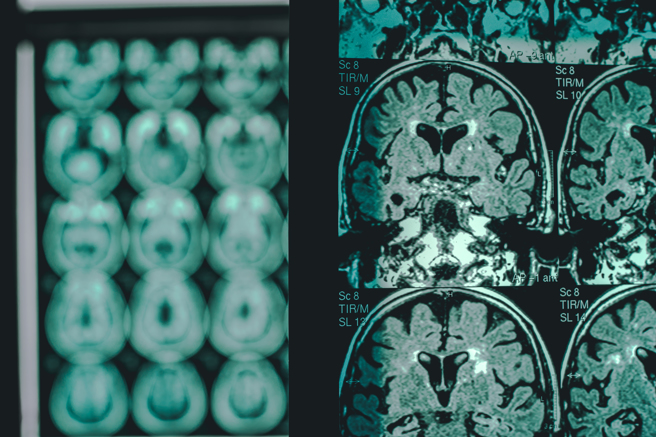

近幾年醫學界對阿茲海默症投入大量資源進行病理研究後,各種研究成果日新月益。最近在權威醫學期刊上發表的研究指出,原先有關阿茲海默症由β-澱粉樣蛋白的斑塊在大腦神經元堆積造成的理論可能有誤,而另一種病理起源理論指向大腦清除廢物機制失調,很可能才是阿茲海默症的病因。這項新發現將使阿茲海默症治療出現新的方向。

過去數十年來研究大多集中於大腦神經元上所形成的β-澱粉樣蛋白斑塊,認為這種異常狀況可能是導致神經元退化的主要病因。此一病理是由發現此症的德國精神病學與病理學家阿洛伊斯.阿茲海默(Alois Alzheimer)醫生透過屍檢觀察所做成的病理推論,此症也因他的研究而得名。

權威學術期刊《自然-神經科學》(Nature Neuroscience)近日以封面文章形式發表一篇研究,對阿茲海默病的β-澱粉樣蛋白假說提出新的挑戰。美國紐約大學格羅斯曼醫學院(NYU Grossman School of Medicine)和納森克萊恩研究所(Nathan Kline Institute)的科學家們在這份新發表的研究報告中指出,在對5種不同實驗模型的小鼠進行觀察後,發現它們的神經細胞在斑塊尚未堆積之前,就已出現自噬機制失調的現象。這種細胞的自噬作用可以理解為細胞日常清除細胞內廢棄物與回收的過程,它利用細胞內的溶酶體將功能受損的元件分解、去除,或進行循環再利用,以保持細胞的健康,維持其穩定運作。